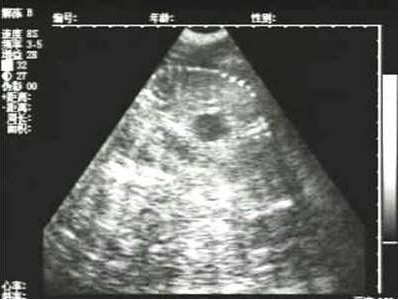

懷孕后期胎兒骨骼圖像

需要注意的是,出現云團狀必須雙側檢查加以確認.根據B超機顯示圖我們大致可以判斷孕齡.圖像呈橢圓或者卵圓形大致為30天左右孕齡;圖像呈橢圓形或者卵圓形外,有明顯發亮骨骼圖像大致為50孕齡左右;圖像囊胚消失,發亮處隱約可見竹節狀東西為成型胎兒骨骼,一般為后期80孕齡以后。一般B超機成像會出現三種顏色,白色、黑色、灰色。白色為密度較高的物體,如骨骼或者結實.黑色一般為液體,包括血液、羊水、組織間隙液體、炎癥病灶等。灰色一般為實質性物質,如肌肉。